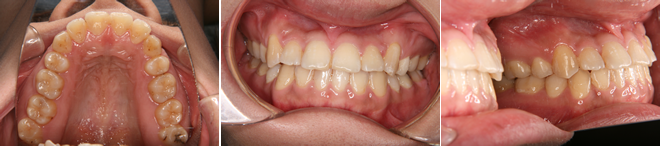

| 主訴 | 前歯が出ている |

| 年齢・性別 | 35歳 / 女性 |

| 治療方針 | 叢生も前歯の突出も大きいケース。小臼歯抜歯だけでは改善できないため、大臼歯の抜歯も行なった。 |

| 抜歯部位 | 上下顎左右小臼歯、左上第1大臼歯(計5本) |

| 使用装置 | マルチブラケット装置 |

| 治療期間 | 36か月 |

| リテーナー | 上顎インビジブル、フィックス、下顎インビジブル |

| 費用 | 885,000円(税別) |